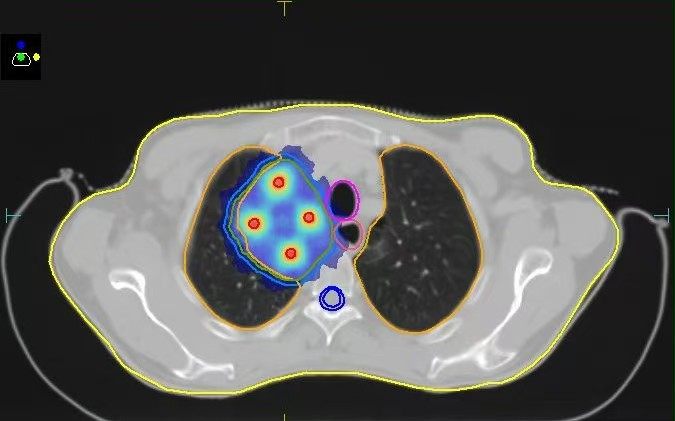

10月27日,南华大学附属第二医院肿瘤中心成功为一名肺癌巨大肿块患者实施了空间分割放疗(SFRT)。这项在双能CT多模态影像引导下完成的技术,不仅是南华大学附属第二医院的首例实践,更一举填补了湖南省在该领域的技术空白,标志着该院肿瘤放疗水平正式迈入“精准制导”新时代。

面对位置特殊、体积巨大的复杂肿瘤,传统的手术、化疗与放疗往往效果有限。传统放疗如同“地毯式轰炸”,在杀伤癌细胞的同时,难以避免地对周围正常组织造成损伤。而此次应用的“空间分割放疗”技术,则实现了从“面”到“点”的跨越,堪称放疗领域的“精确制导系统”。它通过在肿瘤内部同步创建高剂量“峰区”和低剂量“谷区”,形成精密的剂量分布:“峰区”负责对核心顽固区域实施“重点打击”,直接而强力地杀伤肿瘤细胞;“谷区”则在保护正常组织的同时,巧妙刺激免疫反应。二者协同作用,在最大化杀伤肿瘤的同时,犹如为周围的正常肺组织、心脏、脊髓等重要器官穿上“防护甲”,不仅能显著减轻治疗副反应,还能通过产生的“免疫激活效应”触发全身抗肿瘤免疫,为后续联合免疫治疗奠定基础,甚至产生“1+1>2”的协同效果,为以往因肿瘤过大、位置过险而无法耐受放疗的患者提供了新的治疗希望。